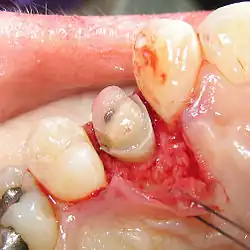

A palatal view of a maxillary premolar during a crown lengthening procedure.